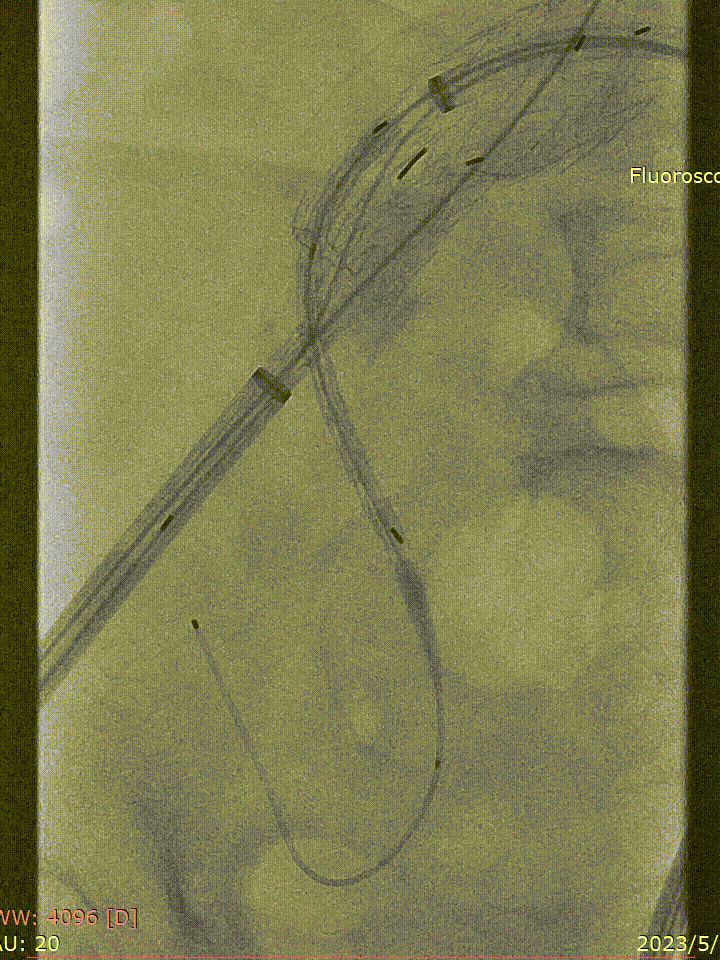

术前情况:74岁男性,肾下腹主动脉瘤,瘤体最大直径66mm,累及双侧髂总,右侧髂内扩张伴开口狭窄,左侧髂内夹层。

手术过程:根据患者及家属要求保双侧髂内,遂计划双侧髂内重建,右侧优先,左侧髂内情况尝试开通。手术中,先进行造影和翻山建立通路。

造影

翻山建立通路

IBE主体就位与右侧髂内重建

随后IBE主体就位,释放主体并翻山DSF鞘至短腿确认髂内情况,确认髂内健康锚定区情况及长度测量,释放髂内分支。对髂内支架狭窄处扩张,输送和释放第二枚髂内分支并手推造影确认通畅,IBE主体及各连接处后扩。

左侧髂内动脉超选与重建

右侧髂内动脉重建完成后,建立对侧翻山通路,再次确认主体位置及左侧髂内动脉情况。左侧髂内超选困难,经反复确认导丝配合导管超选真腔,手推造影确认髂内情况后释放远端VB,释放左侧髂内分支HGB并确认通畅情况。最后按常规EVAR置入腹主动脉支架主体,超选入主体短腿内对接IBE主体释放桥接喇叭腿。

左侧髂内分支HGB释放

手推造影确认通畅情况

术后情况:造影提示动脉瘤完全隔绝,手术成功实现了保留双侧髂内动脉并隔绝动脉瘤的目标,患者病情得到有效控制。

术后造影